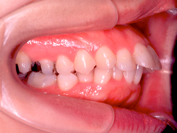

1) 主訴 上の歯が出ており、口が閉じにくい 発音が悪い

2) 診断名 上顎前突

3) 初診時年齢 15歳

4) 治療に用いた装置 ストレートタイブマルチブラケットシステム(018x025スロット)

パラタルバー、前歯はセラミックブラケット

5) 抜歯 左右上顎第一小臼歯、下顎左右下顎第二小臼歯(計4本)